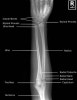

6. Forearm AP view